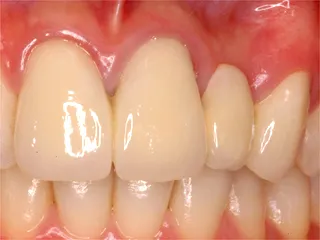

| 自費ブリッジ |

保険のブリッジ

通常のブリッジは 強度を維持するため大きくなります メタルボンドは 適正なサイズで色も自然です ■長所 ・金属が見えない ■短所 ・前後の歯を削り犠牲にする ・高い |